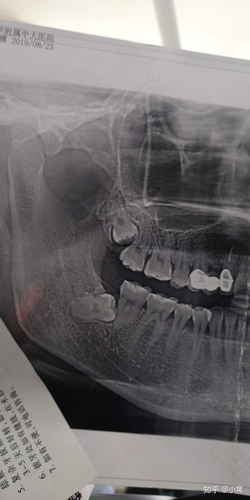

智齿跟一般的牙齿是不一样的,因为它本身生长的位置是比较特殊的,往往都非常贴近自己的面部,所以,在拔牙之前必须要先做拍片检查,在面部有很多神经,要是盲目拔除的话,就可能会导致面部的神经受到影响,甚至可能会导致面瘫问题出现,所以,为了避免出现危险,建议最好是在拔牙之前先拍相关的片子,确定位置以后再看到底要不要拔除牙齿。